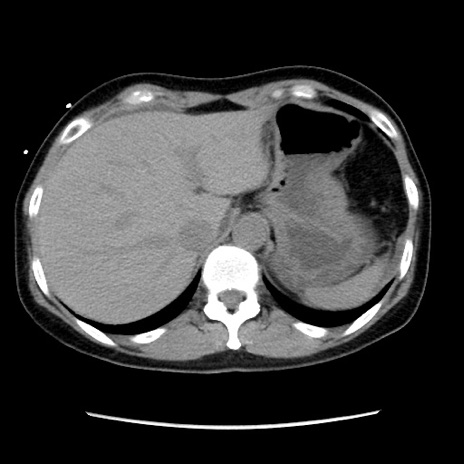

症例10(横断像)

【症例】 50歳代女性

【主訴】 腹痛

【現病歴】前日生レバーを食べた。今朝に排便あり。 昼前に突然発症の腹痛を生じ、当院救急外来を受診した。

【既往歴】 子宮筋腫にてで子宮全摘後

【身体所見】 意識清明、腹部:平坦、軟、下腹部やや左を中心に圧痛・反跳痛あり、筋性防御あり

【データ】WBC 7800、CRP 0.07